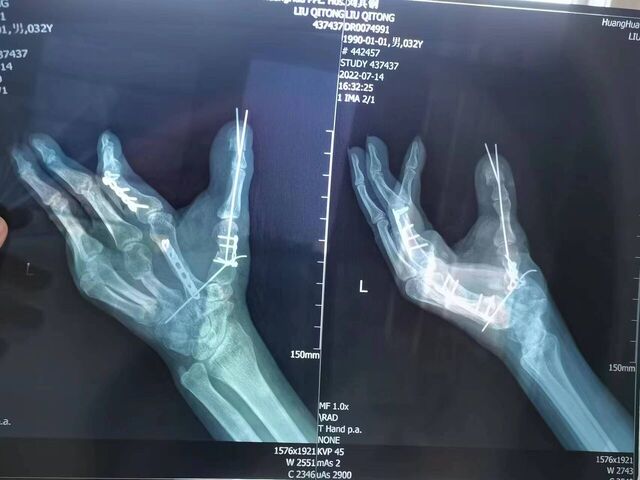

昨天的手术。